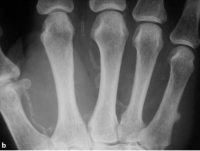

Calcificação das artérias pode ser devido a uma variedade de causas. Estes incluem o diabetes mellitus, hiperparatireoidismo, ateroma, aneurisma, intoxicação por vitamina D e síndrome de Werner. Esta alteração ocorre mais comumente nos membros inferiores. A calcificação arterial é facilmente detectado como calcificações lineares e curvilíneas nas paredes das artérias. Estas características são bem ilustradas na mão de um adulto com extensas calcificações arteriais da palma da mão e dedos nas figuras abaixo.